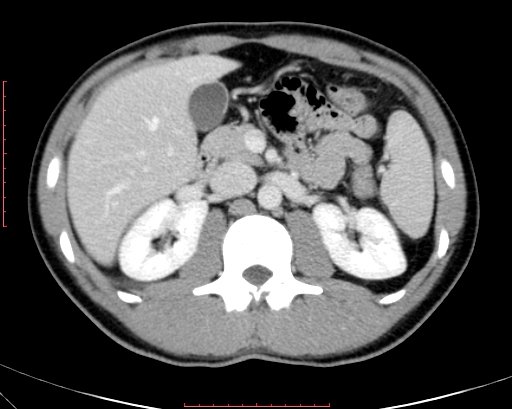

白色文字(排除指定关键词) Imaging Anatomy: interactive PACS-like atlas of radiological anatomy

解剖学模块